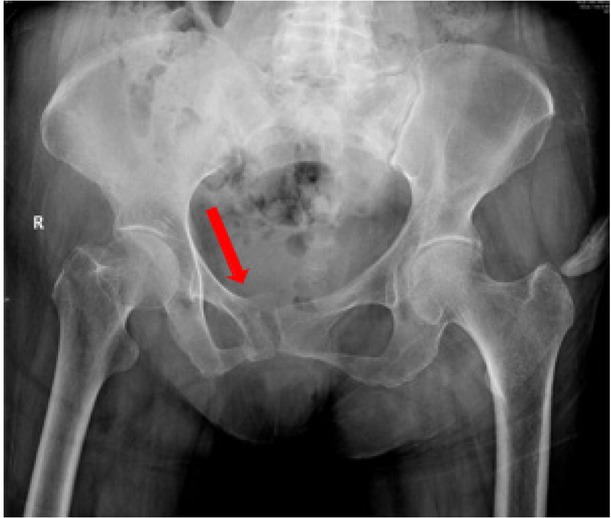

Background: Sacral insufficiency fracture (SIF)is a well defined fragility fracture but insufficient awareness of SIF currently persists among orthopedic,emergency and geriatric physicians. Objective: To heighten clinical characteristics and therapeutic principles of SIF, we presented the diagnostic and treatment process of this case. Case presentation: A 73-year old female without trauma history complained severe pain in low back and pubic symphysis for 20 days. She was diagnosed pubic fracture and lumbar spinal stenosis initially The pelvic X-ray showed mild displacement symphysis pubis fracture without dislocation of the joint (Figure 1) and Dual-energy X ray Absorptiometry (DXA) showed T score -3.2 in lumbar and-3.1in left hip. Conservative treatment,which include immobilization, multimodal pain management and osteoporosis management was carried out with limited efficacy. The patient complained sharp pain when turn over in bed. Pelvic CT was performed for further evaluation and it showed sacrum fracture in both alaes and S1 vertebral body (Figure 2). Diagnosis of insufficient sacrum fracturewas supported by CT, DXA and clinical atrauma history. Considering the prolonged pain after conservative treatment and minimal fracture displacement. Minimally invasive surgery (anterior pelvic ring internal fixator for symphysis pubis fracture combined iliosacral screws for sacrum fracture) was implemented. Visual analogue scale decreased from 8 pre-operation to 4 post operation (Figure 3). Osteoporosis management and rehabilitation was carried out postoperation. Results: The patient achieved full weight-bearing ambulation with mild pain 4 weeks postoperation and anterior pelvic ring internal fixator was moved six months postoperation (Figure 4). Conclusion: 1. Orthopedic, emergency and geriatric physicians should be vigilant against sacral insufficiency fractures in atraumatic elderly patients presenting with low back pain. 2. SIFs could be easily missed on pelvic X-ray because sacrum is poorly visualized and minimal fracture displacementof SIFs. CT and MRI is recommended for diagnosis. 3. The majority of non-displaced SIFs with low level pain could be initially treated conservatively and patients with prolonged pain could benefit significantly from osteosynthesis.

Pelvic X-ray showed mild displacement symphysis pubis fracture without dislocation of the joint.